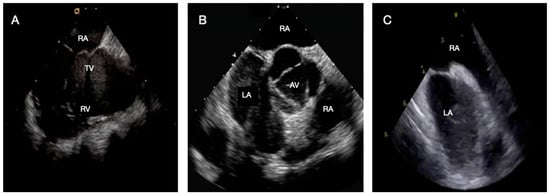

Intracardiac Echocardiography in Structural Heart Interventions: A Comprehensive Overview

by Francesco Leuzzi, Ciro Formisano, Enrico Cerrato, Antongiulio Maione, Tiziana Attisano, Francesco Meucci, Michele Ciccarelli, Carmine Vecchione, Gennaro Galasso and Francesca Maria Di Muro

Intracardiac echocardiography (ICE) is increasingly recognized as a valuable imaging modality in structural heart interventions, offering high-resolution, real-time visualization from within the cardiac chambers. Originally developed for electrophysiologic procedures, ICE has expanded its use across a broad spectrum of structural interventions, including atrial [...] Read more.

Intracardiac echocardiography (ICE) is increasingly recognized as a valuable imaging modality in structural heart interventions, offering high-resolution, real-time visualization from within the cardiac chambers. Originally developed for electrophysiologic procedures, ICE has expanded its use across a broad spectrum of structural interventions, including atrial septal defect (ASD) and patent foramen ovale (PFO) closure, left atrial appendage occlusion (LAAO), transseptal puncture guidance, transcatheter edge-to-edge repair (TEER), balloon mitral valvuloplasty, and both mitral and tricuspid valve therapies. This review outlines the current role and technical principles of ICE, with an emphasis on catheter design, image acquisition protocols, and the emerging potential of 3D ICE. Comparisons with transesophageal echocardiography (TEE) and fluoroscopy are discussed, highlighting ICE’s ability to support minimally invasive, sedation-sparing procedures while maintaining procedural precision. We provide a focused analysis of ICE-guided applications in specific clinical scenarios, emphasizing its role in anatomical assessment, device navigation, and intra-procedural monitoring. Data from recent clinical studies and registries are reviewed to assess safety, feasibility, and outcomes. Practical considerations including operator learning curve, workflow integration, and limitations such as cost and field of view are also addressed. Lastly, we explore future directions including advanced 3D imaging, fusion imaging, artificial intelligence integration, and robotic catheter systems. Full article